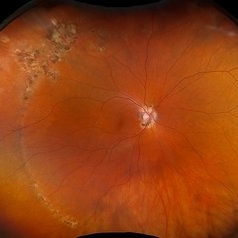

POHS/Schlaegel Lines

POHS/Schlaegel Lines

Sep 19 2024 by Virginia Gebhart

46 year old female with h/o Histoplasmosis. Multiple punched out chorioretinal scars with Schlaegel lines. No evidence of CNV or active inflammation. VA 20/20

Photographer: Virginia Gebhart, Retina Consultants of Carolina

Imaging device: Optos California

Condition/keywords: chorioretinal scar, histoplasmosis, presumed ocular histoplasmosis syndrome (POHS), Schlaegel